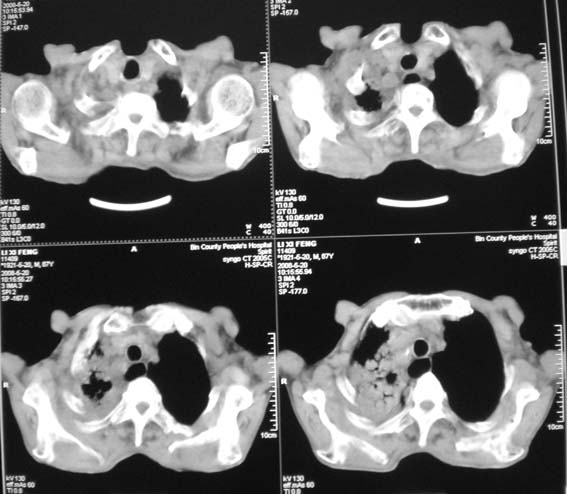

标题: CT12538:男,87岁,请会诊!

男,87岁,咳嗽、发烧、有黄痰,胸片示肺结核。

考虑继发型结核伴右上霉菌球形成。

右肺上叶尖后段片状不规则致密影,密度欠均匀,相邻胸膜肥厚,纵隔内见多发肿大、钙化淋巴结,考虑为结核,部分坏死